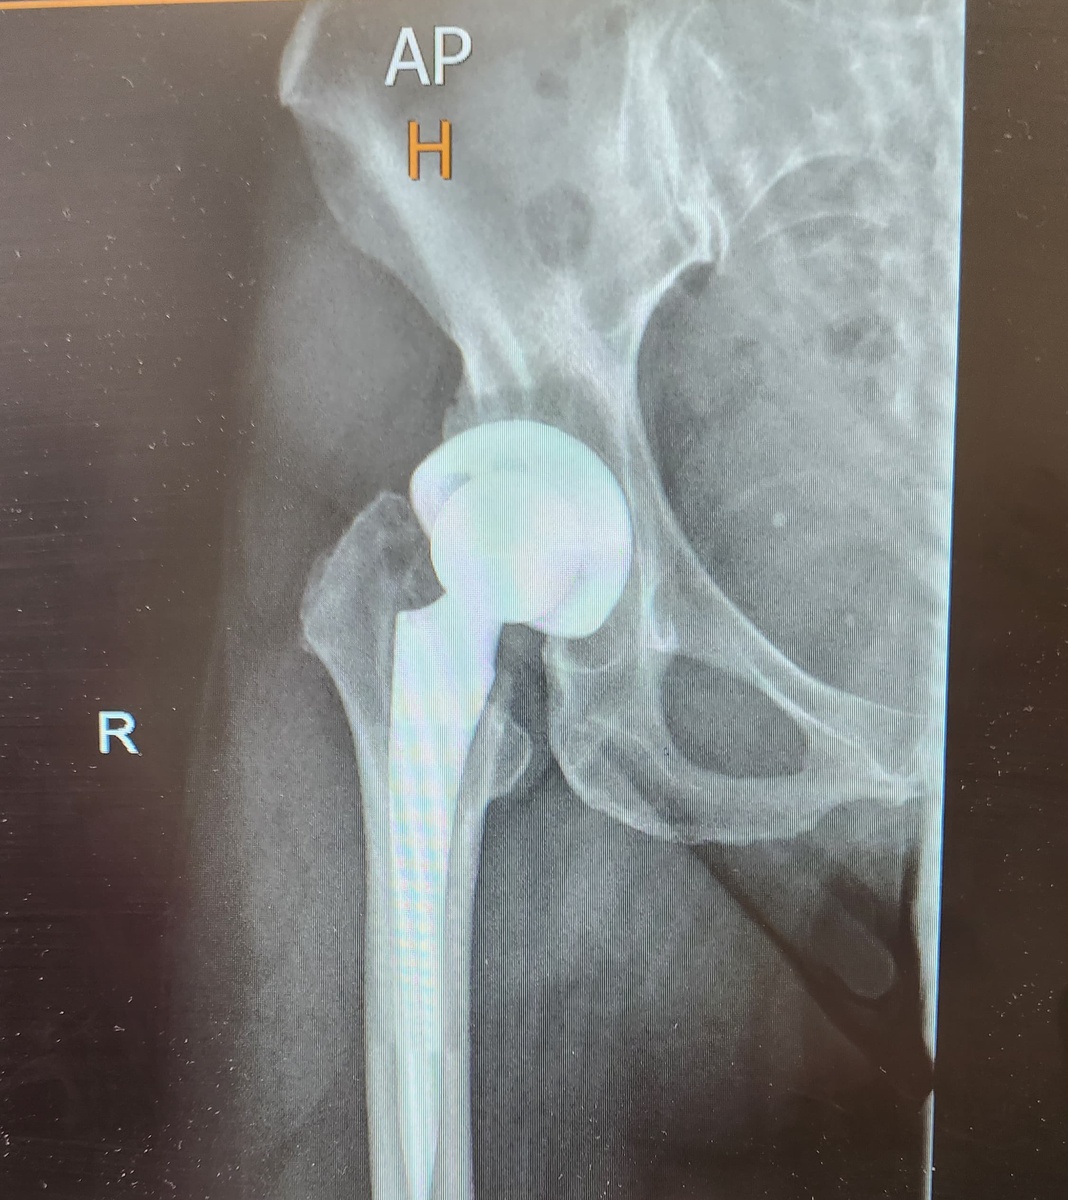

🤔 для тех у кого есть диагноз "артроз" от 3-4 степени и кто прошел через замену сустава. 🕛Время делиться результатами работы. 👩‍🦳Елена, 63 года из Израиля обратилась почти через год после замены тазобедренного сустава. 👇Далее история с её слов: "Я родилась с врождённым вывихом тазобедренных суставов. Мне 63. Год назад заменили правый т/б . До сих пор есть боли. В основном в пояснице. Гиперлордоз При ходьбе правое колено заваливается внутрь-вальгус. Это было и до операции но сейчас больше. Мне не хватает системы У меня ещё до операции перекосило таз. Но я не хотела этого замечать. Я жутко боялась операции. Из-за постоянной боли не могла последние два года заниматься фитнесом и даже плавать. И мой хирург меня ввёл в заблуждение. Сказал что я быстро восстановлюсь . Но с моим диагнозом это не так." 🤝Вот с такой историей и такими результатами мы и начали работу. Стоит сказать, что с операцией Елена тянула до последнего и согласилась на неё когда боль была совсем невыносимой. 👇

👩‍🦳Елена, 63 года из Израиля обратилась почти через год после замены тазобедренного сустава.

"Я родилась с врождённым вывихом тазобедренных суставов. Мне 63. Год назад заменили правый т/б . До сих пор есть боли. В основном в пояснице. Гиперлордоз

При ходьбе правое колено заваливается внутрь-вальгус. Это было и до операции но сейчас больше.